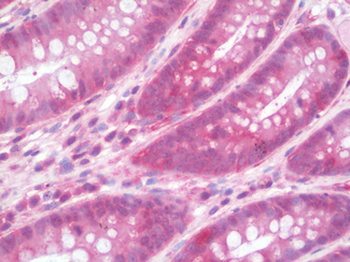

Immunohistochemistry of paraffin-embedded human colon cancer tissue using IL36RN antibody